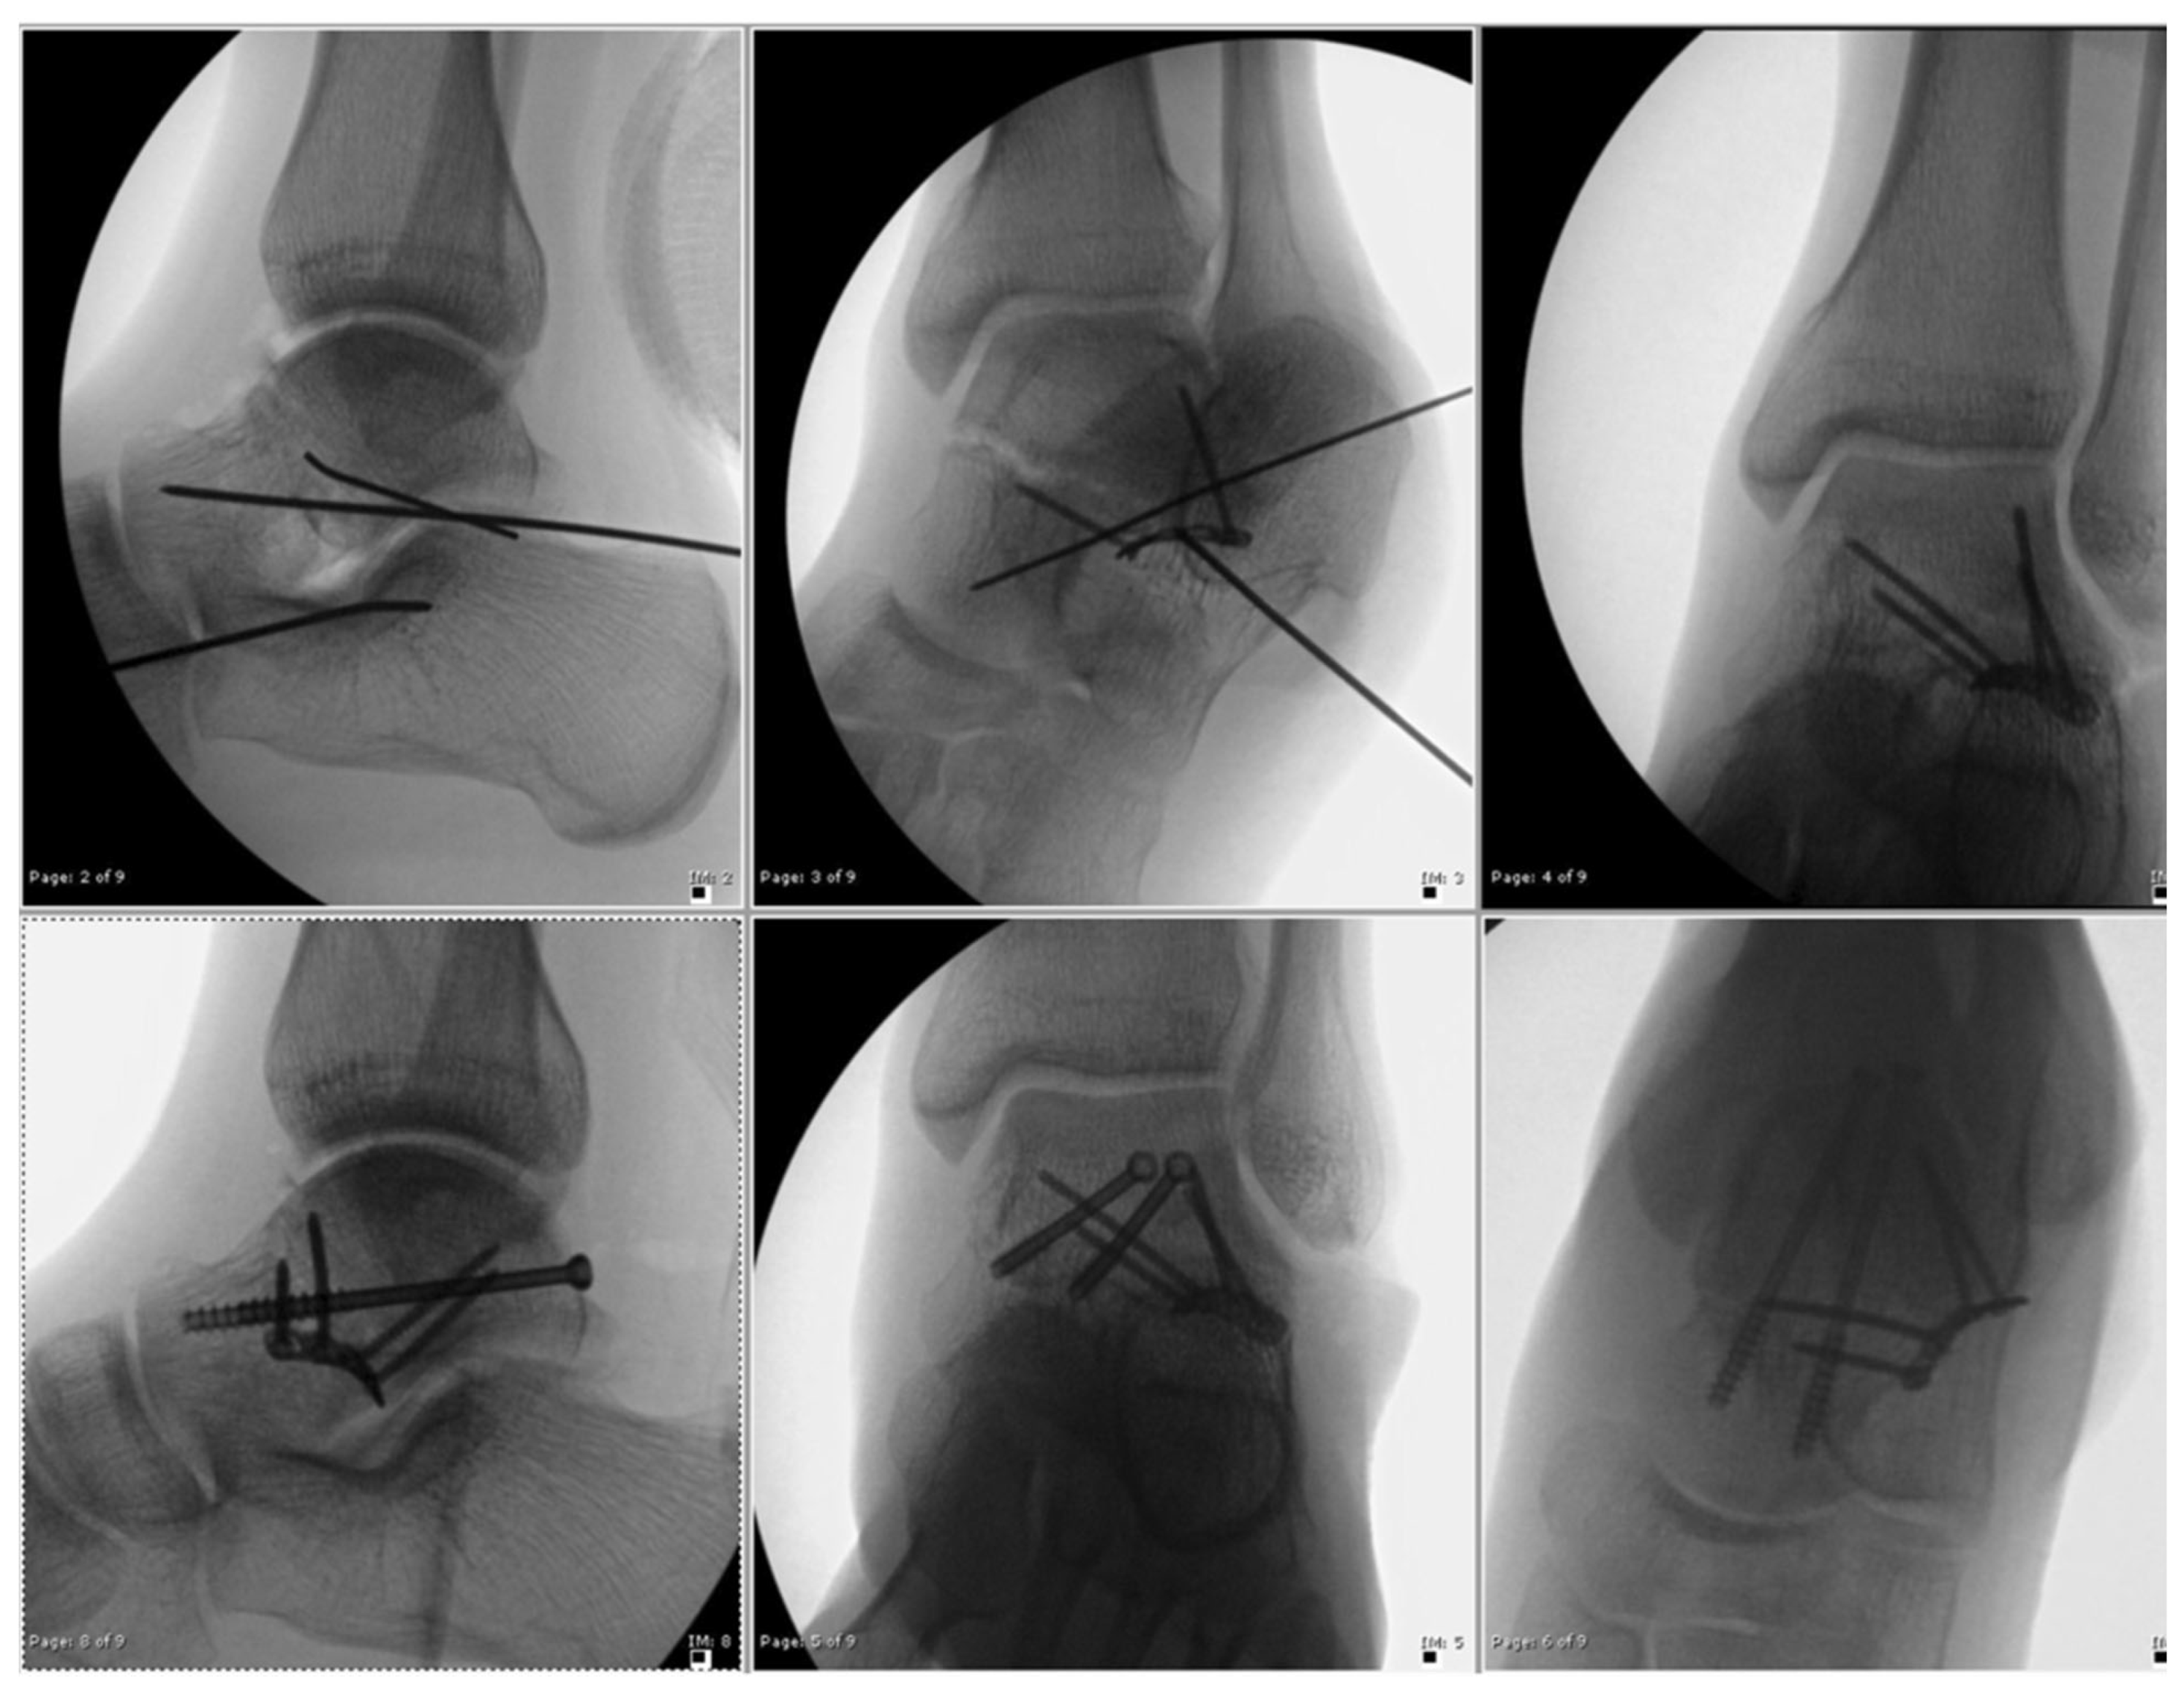

2.1. Surgical Technique